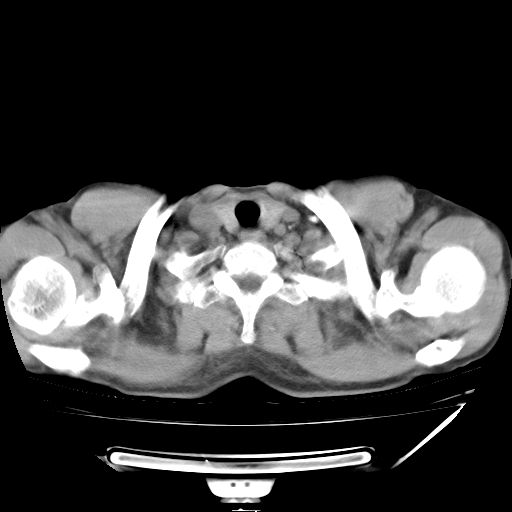

男,59岁,“结核性胸膜炎”30余年,胸部经常疼痛,多次x检查提示“肺部”炎症。腹部疼痛5日,b超提示:“肝内短管结石,余显示不清,建议进一步检查。”

两肺结核并右侧胸腔积液;脾脏、腹腔及腹膜后淋巴结结核[陈旧性];肝内胆管结石

胸部腹部都是结核(双肺。纵隔淋巴结,肝脏,脾脏,肠系膜)